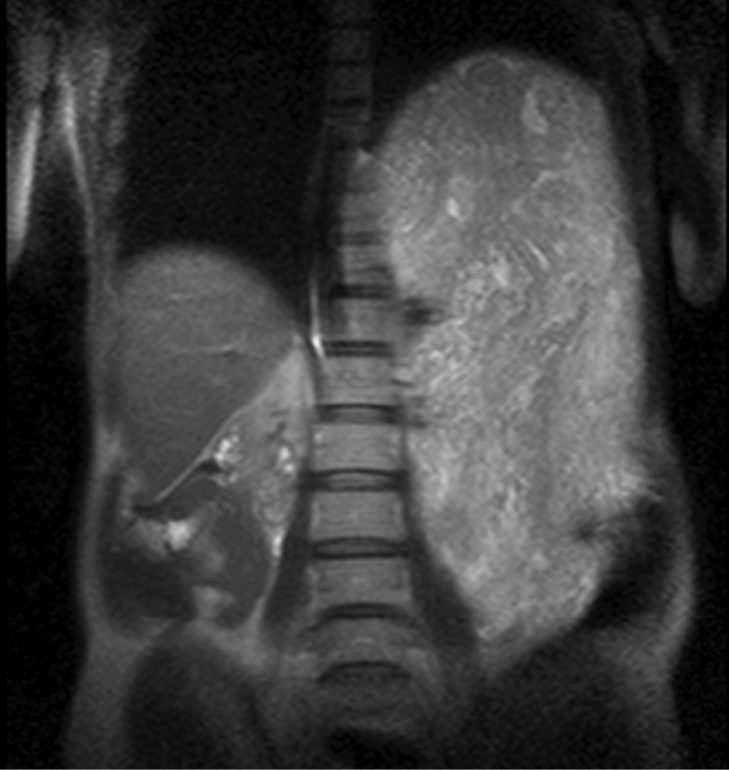

По данным компьютерной томографии (КТ) брюшной полости определялось массивное образование размерами 54×34×22 см, относительно однородной структуры. Опухоль смещала левый купол диафрагмы с левым легким вверх с уменьшением его объема наполовину. Петли кишечника, печень, аорта были смещены вправо. При ангиографии кровоснабжение опухоли осуществлялось за счет желудочно-сальниковых сосудов (рис. 1, 2).

Рис. 2. Гастроинтестинальная стромальная опухоль большого сальника. Опухоль смещает купол диафрагмы вверх с компрессией левого легкого.